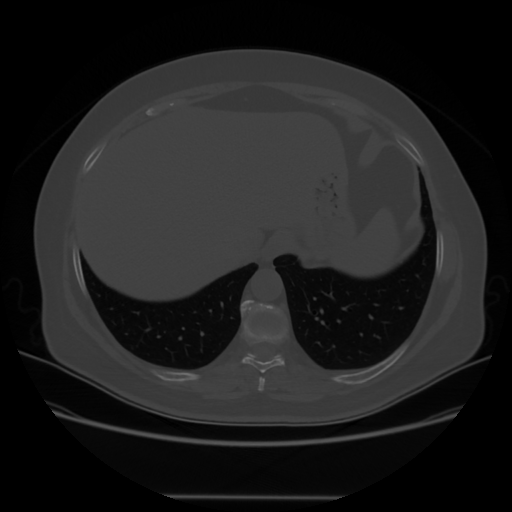

Generated VENOUS CT scan (A→B translation)

Full window (WL 1023.5, WW 4095 β†’ Low βˆ’1024, High +3071)

Lung window (WL -600, WW 1500 β†’ Low βˆ’1350, High +150)

Mediastinum window (WL 40, WW 400 β†’ Low βˆ’160, High +240)